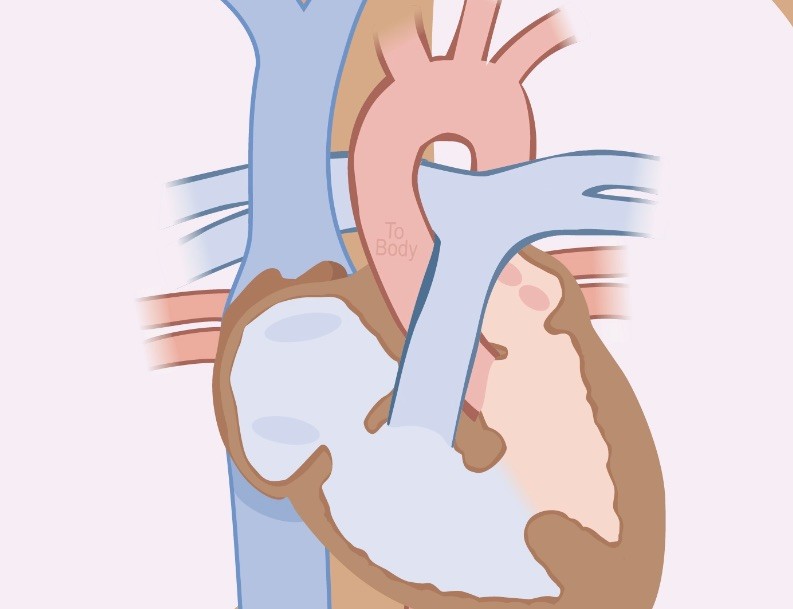

סקירת מערכות נועדה לגלות מומי לב. למעשה, כבר בבדיקת שקיפות עורפית ניתן לקבל רמזים למום בלב. אפשר וצריך לגלות פגם במחיצה בין העליות (ASD), בין החדרים (VSD), או פגם החלפה של העורקים הגדולים. ראה חוזר משרד הבריאות בעניין

בשנת 2013 עודכנו ההנחיות את מה עוד יש לסרוק בסקירת מערכות: את מוצא כלי הדם, את אבי העורקים ואת עורק הריאה.

(ב) פגם במחיצת הבין עלייתית Asd

(ג) פגם במחיצה הבין חדרית Vsd

Vsd

vsd הנו חור במחיצה הבין חדרית. ההשלכה יכולה להיות אי ספיקת לב. חשד ניתן לקבל מהזעות מרובות של התינוק. ניתן לאבחן VSD כבר בשבוע 12. לעתים בשילוב איוושה. איוושה היא צליל ״שגוי״ של זרימת דם בהאזנה ללב.

Asd

ASD הוא חור במחיצה שבין העליות. הסימפטומים כמעט ואינם מורגשים. גם כאן קיימת התוויה לסגירת החור. בקוטר של 4 עד 5 מ"מ 56% הראו סגירה ספונטנית, 30% נסוגו. מנגד, בקוטר של 10 מ"מ המום לא נסגר ספונטנית.